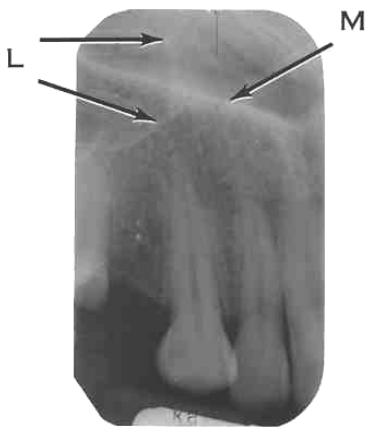

25. What is shown by M?

26. What is shown by L?

27. What is L showing?